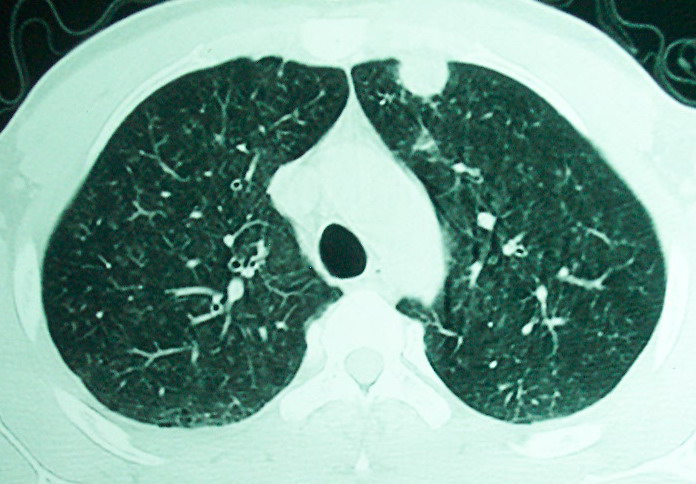

m      37y      发热   咳脓痰月余      ct肺脓肿但住院抗炎治疗后双肺内结节不知该如何解释

治疗后见左肺下野病灶较前缩小但双肺内结节影似无变化请较各位老师该如何下结论    治疗前wbc14.5 治疗后wbc 11.0

血源性肺脓肿,一般由原发感染灶引起脓毒败血症,在肺部形成小脓肿,病变变化快,容易形成肺气囊,脓气胸,主要与转移瘤鉴别,通过临床病史可分

结合临床发热,咳痰考虑为血源性肺脓肿,不过双肺结节又在肺的边缘,还是小心一点,抗炎后复查吧

我看是不是可以两元化来解释,左肺下叶还是肺脓疡,而其余病灶考虑肺癌伴肺内转移,我看右肺上叶尖段病灶可见明显毛刺改变为原发病灶.

左下肺病灶除了明显的厚壁空洞 气液平外,明显见壁结节,另两肺多发小结节,综合考虑:左下肺周围性肺癌伴肺内转移.

除了肺内多发结节和左肺下叶的浓疡病灶,还应注意满肺散在的小结节影,还有右上肺前段支气管内膜不光整这些细节,结合病史,肺内多发结节应考虑结核性肉芽!

如果你仔细的同层面对比,你会发现所有的病灶均有比较明显的吸收、缩小。病变的形态,特别是脓肿的形态、壁的厚薄、内壁均有很大的变化,均在往好的方面发展。与临床症状、血像均符合,治疗效果比较显著,就是肺脓肿并双肺的化脓性炎症灶。